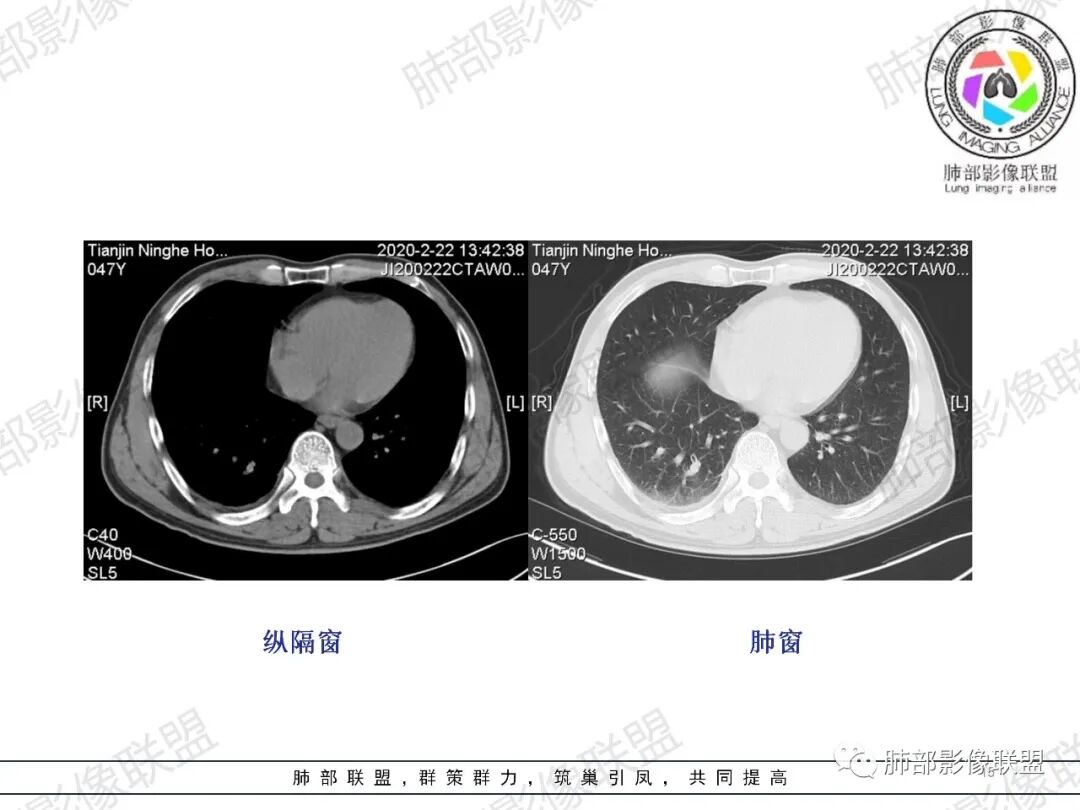

杨泽锋:右肺尖病灶由结节赢、索条影、斑片状影,考虑结核右肺下叶胸膜下楔形斑片状影,因为临床上有胸痛,发热又不明显,首先会想到肺梗,建议增强看看

马春平(张家港市一院胸外科):中年男性、低热、痰血、胸痛 、血象高,右上叶多发结节、疑似空洞、渗出、纤维条索、树芽,右下肺胸膜下与胸膜平行GGO肺泡和小叶间隔增厚,考虑二元论:右上结核、右下肺梗

一切∮随缘:右肺肺尖段多发结节片状高密度影,部分伴有反晕征,边界欠清楚,部分伴有纤维索条,支气管显示欠佳,小叶间隔增厚,周围血管束增粗,(考虑结核可能)右肺下叶胸膜下片状磨玻璃影,与胸膜相贴,与肺组织交界面清楚,实性偏少,考虑:肺栓塞?病毒?OP?

王秀仙:右肺上叶可见结节及斑片影,部分呈反晕征,边缘清晰,右肺下叶后基底段胸膜下磨玻璃样实变影,呈扇形,内部见细网格,右肺上叶考虑结核。右肺下叶考虑肺栓塞,鉴别病毒肺炎。

小兜:男,47岁,胸闷气短入院,一天前无明显诱因胸闷气短伴呼吸困难,夜间出现右侧胸痛,与呼吸及体位有关,曾有一次痰中带血。CT示右肺上叶尖段多发结节,条索影,可见树芽征及反晕征。右肺下叶胸膜下片状密度增高影,宽基底与胸膜相连,成扇形。综合考虑右肺上叶尖段结核可能;右肺下叶肺栓塞?病毒性肺炎?

琦遇:右肺上叶结核基本明确,考虑活动性,有钙化、反晕征、结节、斑片、纤维索条;右肺下胸膜下GGO,内大小网格,胸膜增厚,患者胸痛,咯血,首先考虑PE,下一步增强CTPA以明确

飞鹰行动:中年男性、低热、痰血、胸痛 、血象高,右上叶多发结节,磨玻璃影、疑似空洞、渗出、纤维条索、树芽,有烟花样改变,右下肺胸膜下与胸膜平行GGO肺泡和小叶间隔增厚,考虑二元论:右肺上叶结核、右肺下叶梗塞?建议CTA检查。

水晶石头:患者中年男性,胸闷、气促1天。伴右胸痛及痰中带血。否认结核、心脏疾病等病史。查体无特殊。完善血常规白细胞计数、中性粒细胞百分比及C反应蛋白升高。心电图、B超、凝血功能、降钙素原、脑钠肽正常。胸部CT:右肺上叶尖段多发结节、斑片、纤维条索影,见小叶间隔增厚及反晕征。右肺下叶后基底段胸膜下片状磨玻璃影,见小叶内间隔增厚。右侧胸膜增厚,未见明显淋巴结增大。综合考虑右上肺结核病变,右下肺肺栓塞。鉴别病毒性肺炎及恶性病变。

张延军:右肺上叶多发大小不等结节,部分界清,反晕征(+),下叶胸膜下磨玻璃影,纵膈窗似较对称血管细,结合咳血症状,考虑栓塞

右上叶,多灶性、多态性,烟花征,结核应该没问题